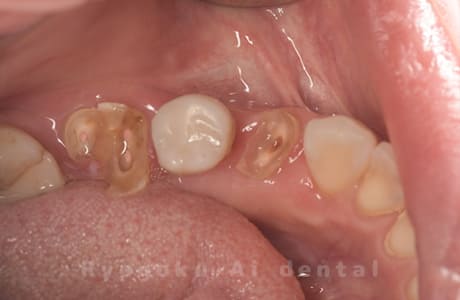

Case22

- 重度カリエス

- 治療内容

- クラウンレングスニング治療

- 治療費用

- 110,000円(別途被せ物)

他院で抜歯を宣告され、当医院で保存希望でご来院された患者様です。クラウンレングスニングを行い、保存しました。大変満足されました。